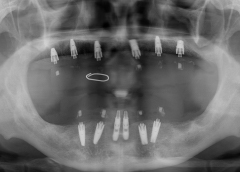

• Tình trạng mất răng:Mất toàn bộ răng hàm trên, từng mang hàm tháo lắp.

• Phương hướng điều trị:Phục hình lại toàn bộ hàm trên bằng phương án cấy ghép Implant All On 6. Cắm 6 trụ Implant và phục hình hàm sứ cố định.

• Trụ Imlant sử dụng:Implant Straumann Thụy Sỹ và răng sứ Zirconia Đức.

• Cấy ghép 6 trụ implant hàm trên loại Implant Straumann Thụy Sỹ

• Phục hình răng sứ Zirconia Đức